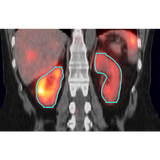

MIM SurePlan MRT's automated segmentation can significantly reduce the time required to generate organ volumes including the liver and kidneys. Industry-leading PET and segmentation tools are also available for tumors and other volumes of interest.